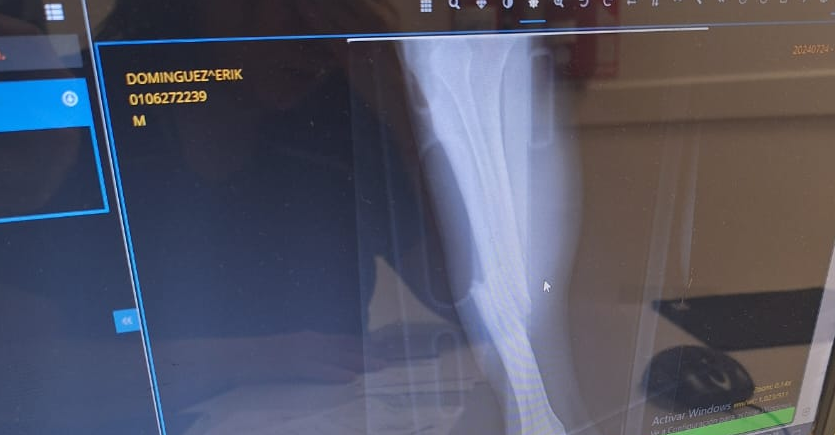

Erik fue trasladado inmediatamente al hospital de Complejidad VI donde se confirmó la gravedad de la lesión que afectó tibia y peroné de la pierna derecha del deportista. El adolescente debe ser sometido a una intervención quirúrgica dado que hay desplazamiento del hueso.